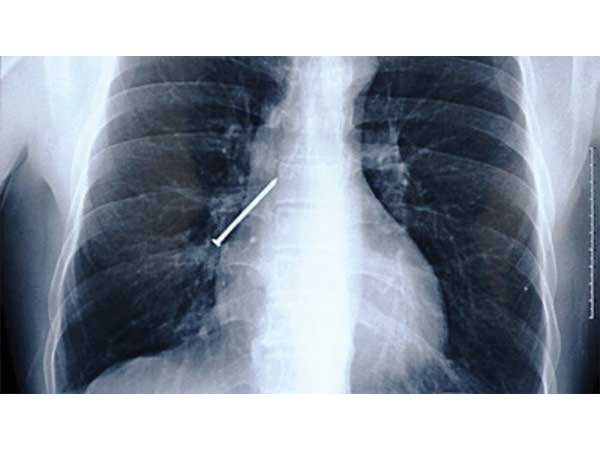

ಮೊಳೆ

ಚೀನಾದ Li Xiangyang ಎಂಬ ಈ ಬಡಗಿ ಅಕಸ್ಮಾತ್ತಾಗಿ ಮೊಳೆಯನ್ನು ನುಂಗಿಬಿಟ್ಟಿದ್ದ. ಸಾಮಾನ್ಯವಾಗಿ ಬಡಗಿ ಮತ್ತಿತರ ಕೆಲಸಗಾರರು ಎತ್ತರದ ಸ್ಥಳಗಳಲ್ಲಿ ಕೆಲಸ ಮಾಡುವಾಗ ಅಗತ್ಯವಿದ್ದ ಮೊಳೆ, ಸ್ಕ್ರೂಮೊದಲಾದವುಗಳನ್ನು ಹಲ್ಲಿನಲ್ಲಿ ಕಚ್ಚಿಕೊಂಡು ಒಂದಾದ ನಂತರ ಇನ್ನೊಂದನ್ನು ಹೊಡೆಯುತ್ತಾ ಹೋಗುತ್ತಾರೆ. ಹೀಗೇ ಒಂದು ಮೊಳೆ ಇದ್ದಾಗ ಯಾವುದೋ ಯೋಚನೆಯ ಗಡಿಬಿಡಿಯಲ್ಲಿ ಮೊಳೆ ನೇರವಾಗಿ ಗಂಟಲಿಗೆ ಇಳಿದು ಅಡ್ಡಲಾಗಿ ಚುಚ್ಚಿ ಅನ್ನನಾಳವನ್ನು ಹರಿದು ಶ್ವಾಸಕೋಶಕ್ಕೆ ಚುಚ್ಚಿಕೊಂಡುಬಿಟ್ಟಿತ್ತು. ತಕ್ಷಣ ಆಸ್ಪತ್ರೆಗೆ ಕರೆದೊಯ್ದು ಶಸ್ತ್ರಚಿಕಿತ್ಸೆಯ ಮೂಲಕ ಮೊಳೆಯನ್ನು ಹೊರತೆಗೆದ ಬಳಿಕ ಈತ ಚೇತರಿಸಿಕೊಂಡಿದ್ದಾನೆ.

Image courtesy